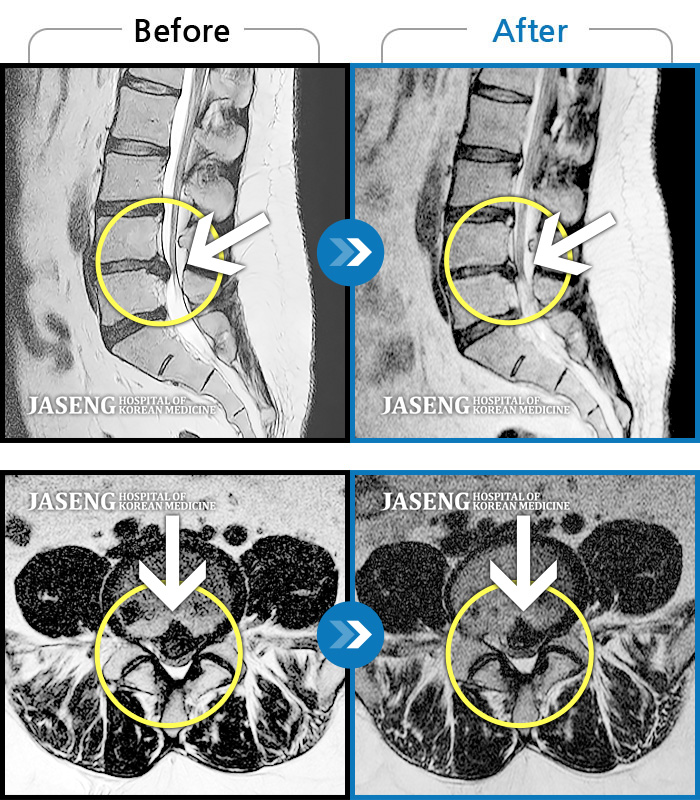

허리디스크

인천 · 조남훈 원장

허리가 너무 아프고 다리가 저려요.

촬영시기

2018.04.23 ~ 2025.12.05

2025.12.19